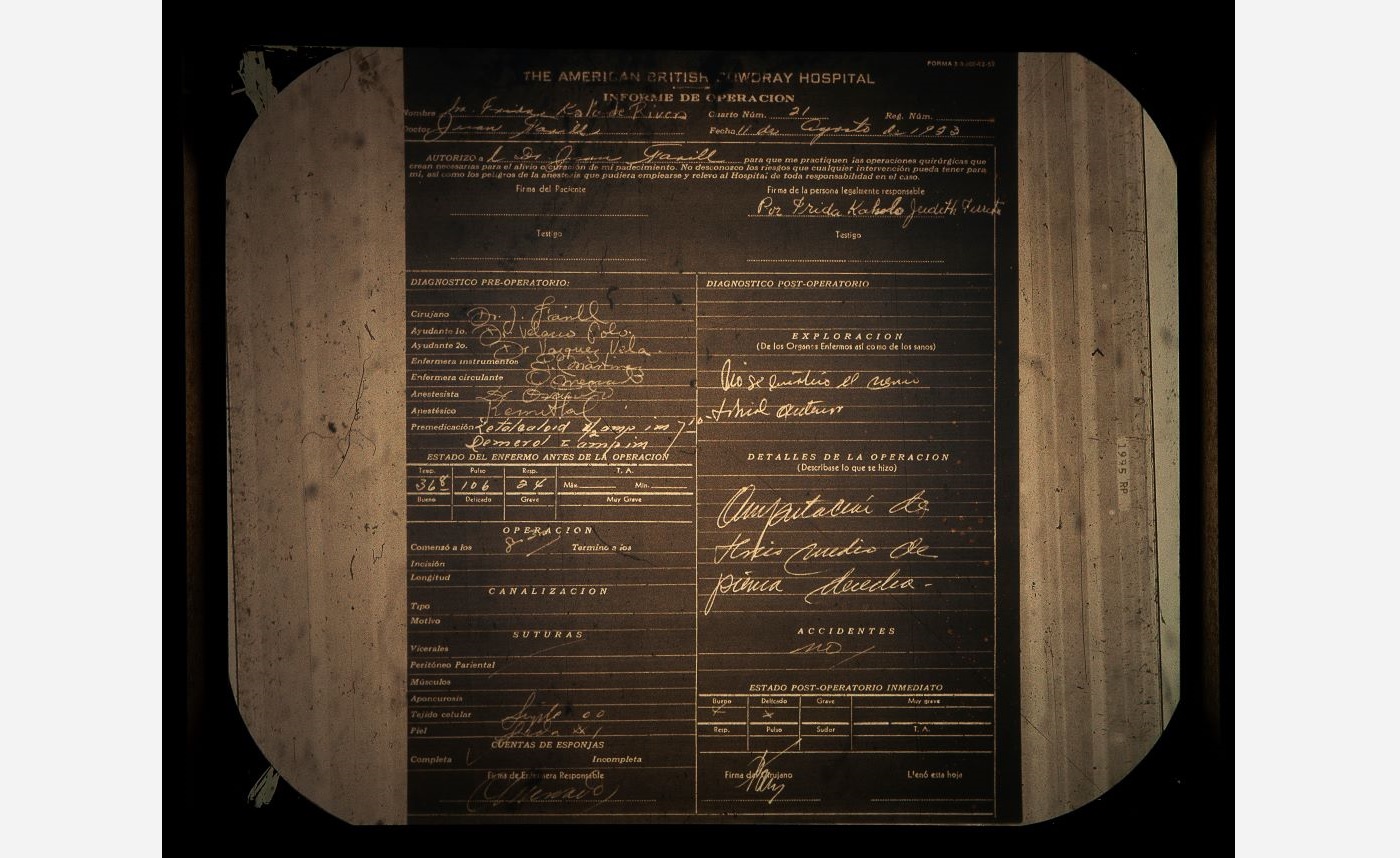

The last major recorded surgery Frida Kahlo underwent was an amputation of her right leg, on 11 August 1953—less than a year before her passing. The amputation was performed due to Frida having been diagnosed with gangrene—a medical condition that involves the death of body tissue due to a lack of blood flow or a serious bacterial infection.

Cristina Kahlo Alcalá, American British Cowdray Hospital File (Clinical Sheet), 1953, 2023, lightbox installation, Courtesy of the artist and Centro Médico ABC Historical Archive. © Cristina Kahlo

Cristina Kahlo Alcalá, American British Cowdray Hospital File (Operation Report), 1953, 2023, lightbox installation, Courtesy of the artist and Centro Médico ABC Historical Archive. © Cristina Kahlo

Cristina Kahlo Alcalá, American British Cowdray Hospital File (Operation Report), 1953, 2023, lightbox installation, Courtesy of the artist and Centro Médico ABC Historical Archive. © Cristina Kahlo -

The Hospital

The ABC hospital was where Frida stayed for almost a year in 1950—undergoing seven spinal surgeries—and where in 1953 her lower right limb was amputated under the care of Dr. Juan Farill. Frida was treated at the ABC hospital until her passing in 1954.